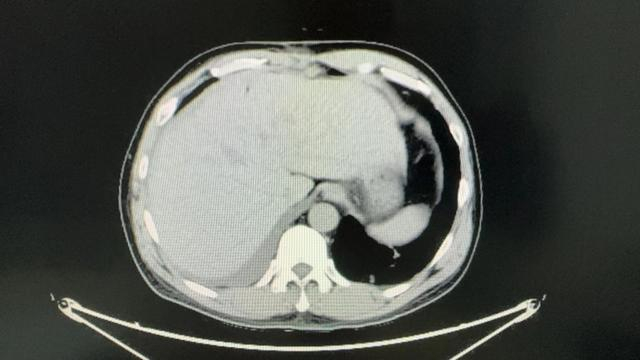

在住院期间,患者查上腹部CT后提示肝左右叶交界处肝癌,经同济医院肝胆外科中心主任谭蔚锋会诊后进行后续治疗。

术前影像学资料

1月4日行腹腔镜下特殊肝段切除术(肝中叶IVA+VIII段),术中病理为肝细胞癌。